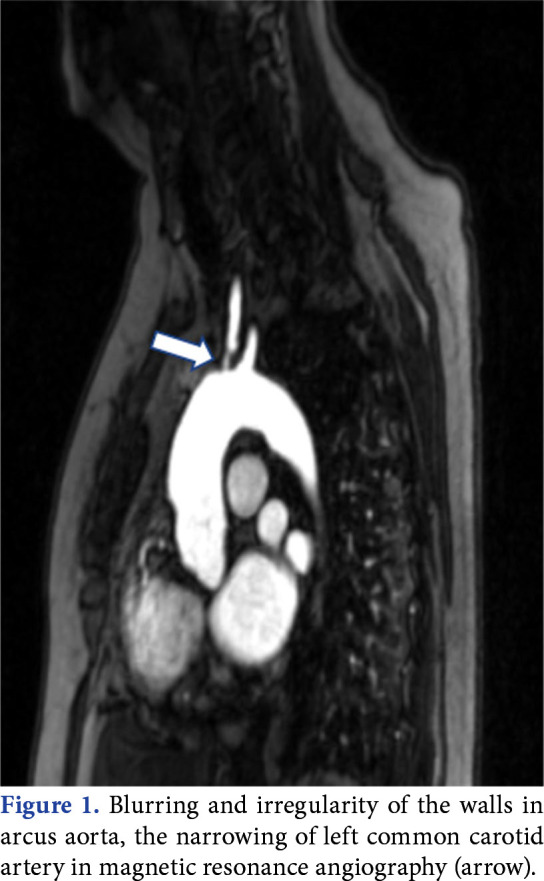

Takayasu arteritis (TA) is an uncommon chronic inflammation of blood vessels. It can occur with a range of clinical manifestations. However, low back pain is uncommonly defined as the initial symptom of TA. In this article, we report a 53-year-old woman who presented with low back pain and was diagnosed with TA after a detailed clinical examination and further evaluations. A thorough history and detailed physical examination can help to recognize the underlying cause of low back pain. Takayasu arteritis should be kept in mind as an alternative diagnosis while evaluating low back pain with high inflammation parameters, particularly in women.